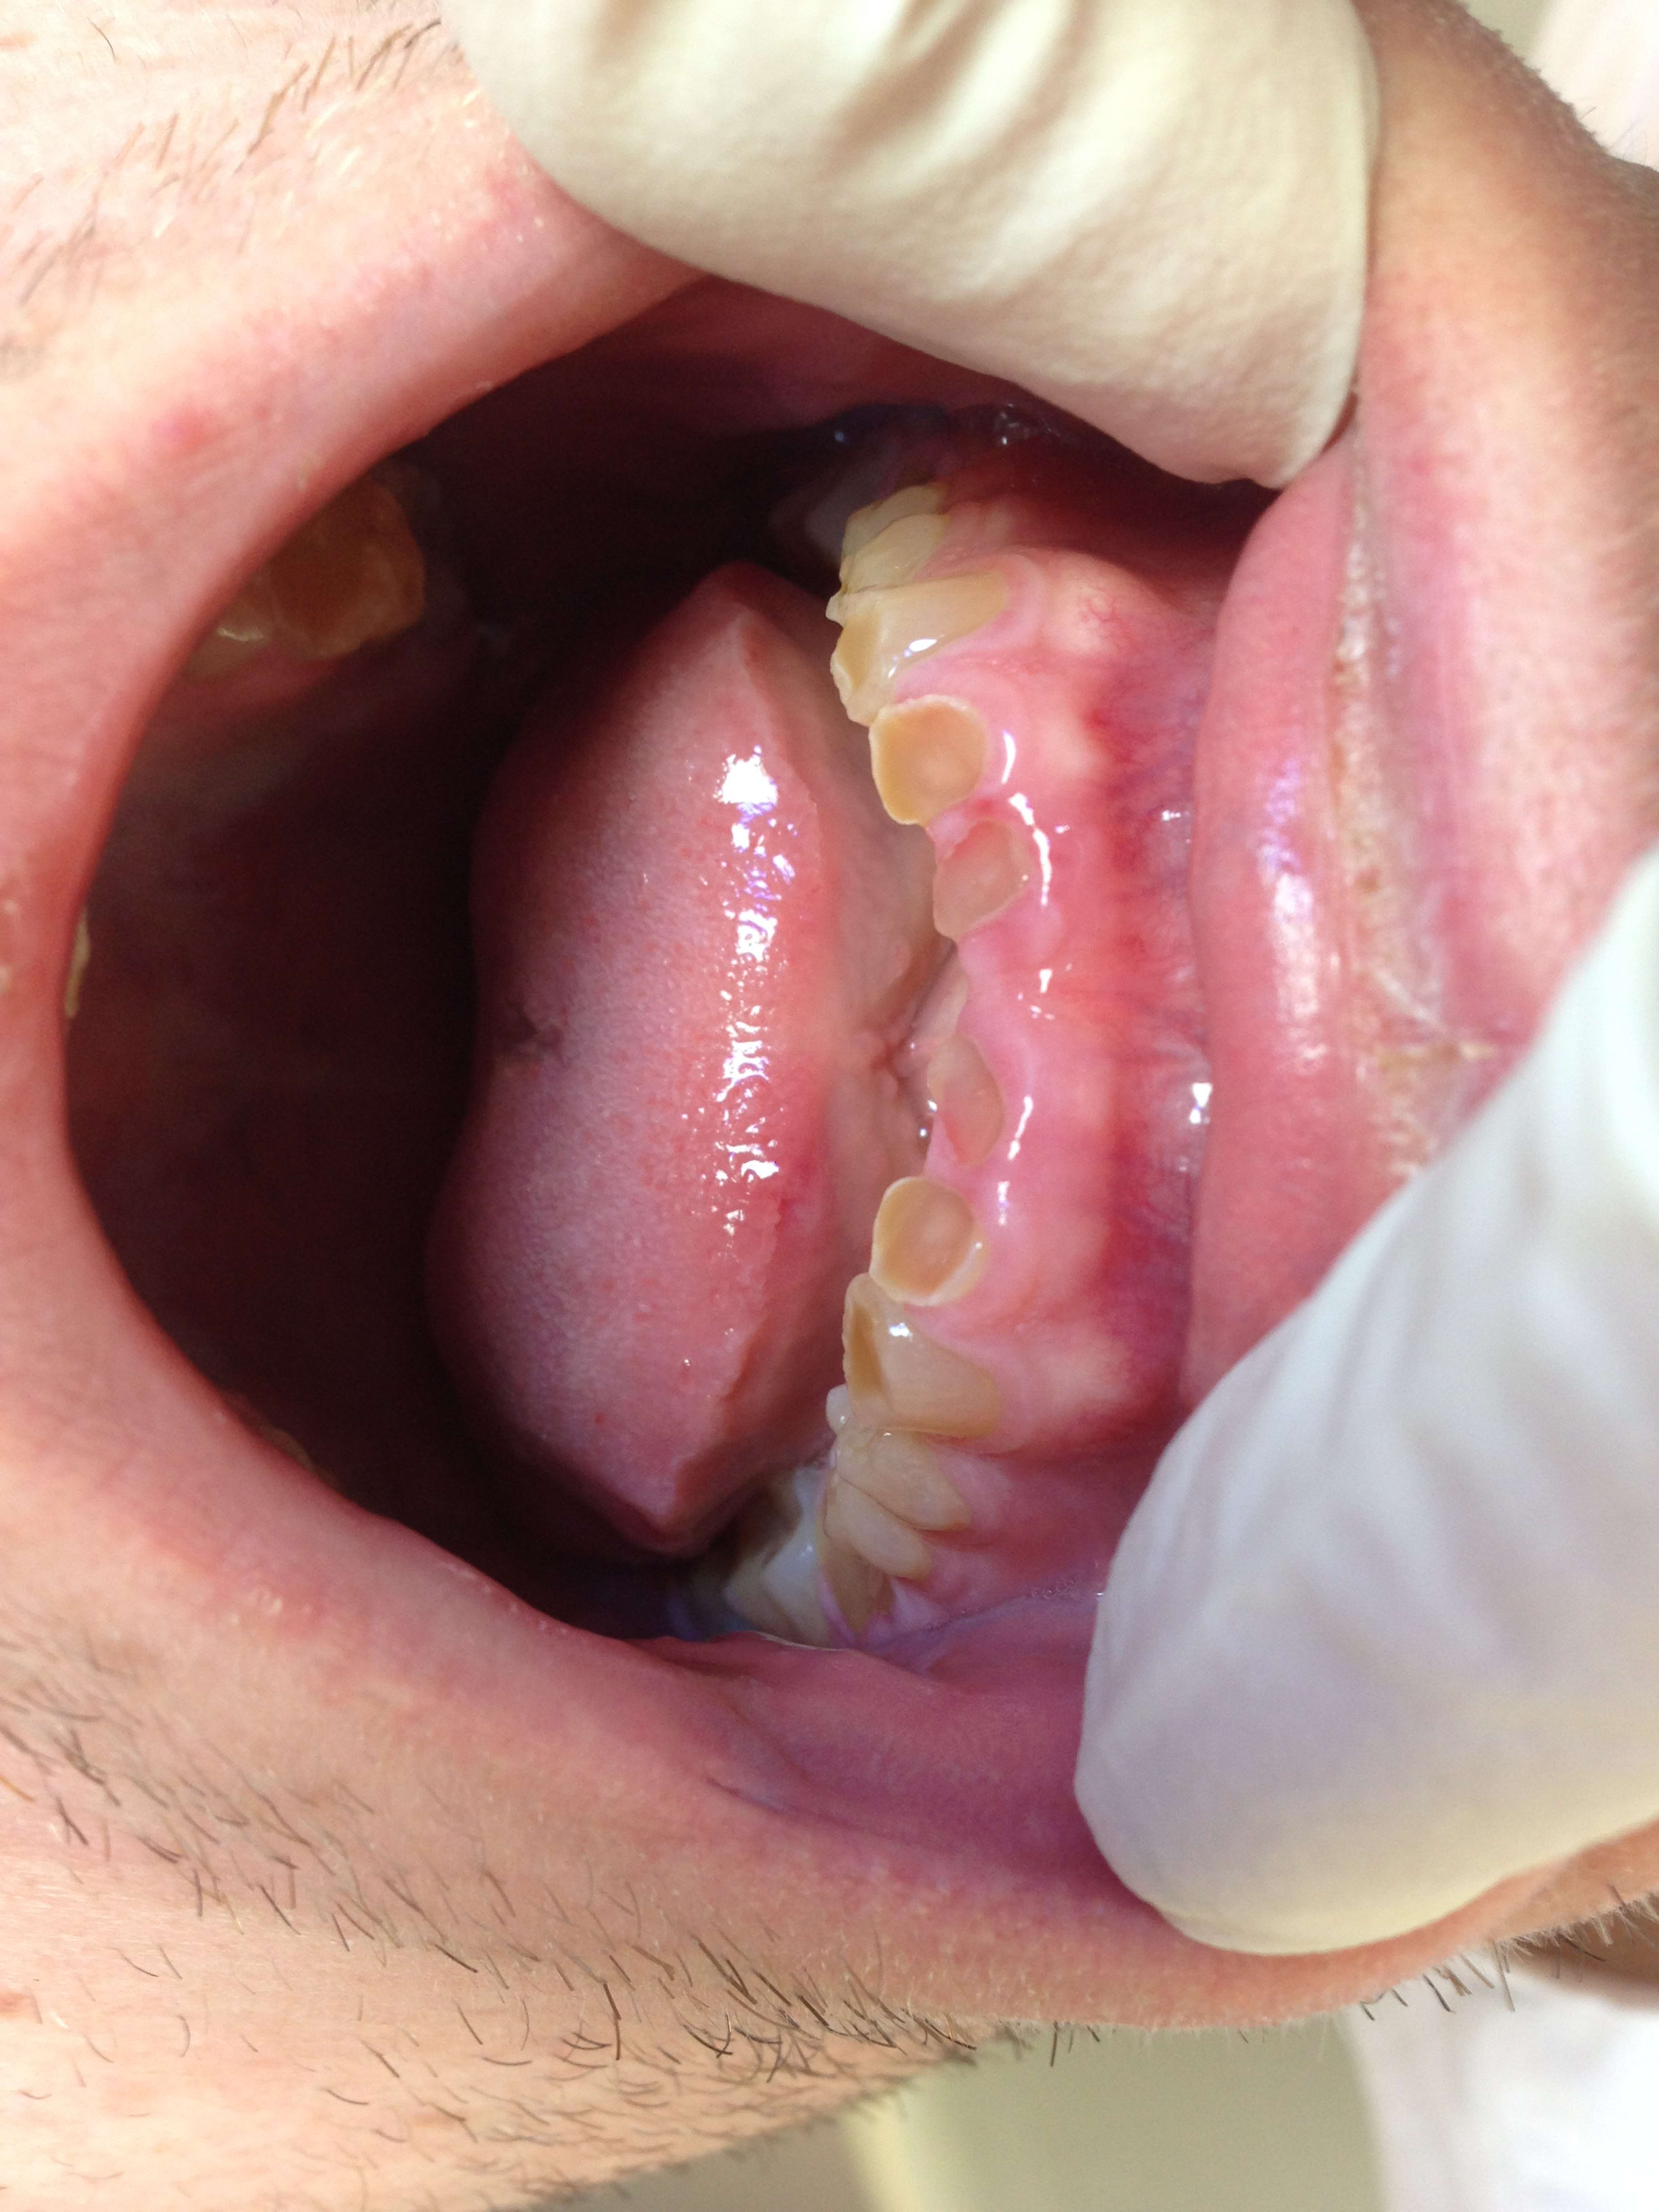

Regardez moi ça bande de vieilles branches : patient de 21 ans et remarquez l'usure. Jamais vu une telle usure aussi rapide chez un bruxeur . Il joue des castagnettes avec ses dents toutes les nuits me dit il

alcoolo qui vomit ou qqc de ce genre, RGO, sinon pb d'émail.

amphètes, cathinones diverses ou autre truc en poudre.

Pour moi c'est un problème d'email (pas ou peu d'email ) + bruxisme